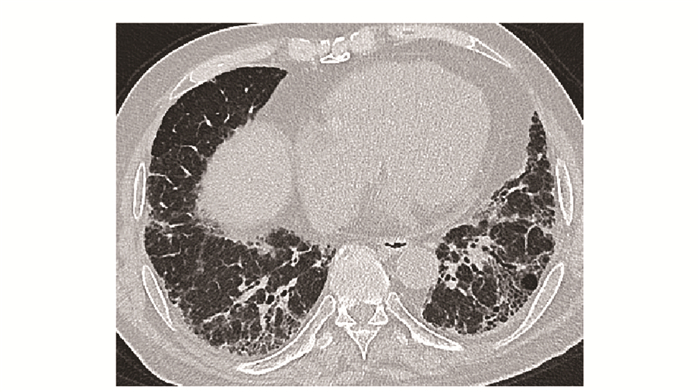

• 摘要: 结缔组织病累及呼吸系统可表现为间质性肺疾病、弥漫性肺泡损伤、肺泡出血、肺血管病变、胸膜病变及气道病变等。其临床表现缺乏特异性, 肺功能和胸部CT是最常用的检查手段。不同结缔组织病累及呼吸系统的影像特征具有相似性, 但又各具特点。本文就结缔组织病呼吸系统受累相关影像表现进行概述, 以提升读者的认知并指导临床实践。

Abstract: Respiratory manifestations of connective tissue diseases include interstitial lung diseases, diffuse alveolar injury, alveolar hemorrhage, pulmonary vascular lesions, pleural lesions and airway disease. Their clinical symptoms were not specific. Pulmonary function test and chest computed tomography come to be the most frequently applied examinations. Different connective tissue diseases involving respiratory system have not only common features but also characteristic imaging patterns. In this paper, imaging manifestations of respiratory diseases associated with connective tissue diseases were reviewed, so as to improve readers' recognition of the diseases and guide clinical practice.